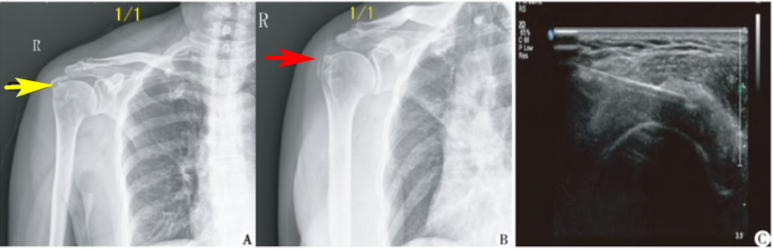

왼쪽에서 첫번째 그림은

도침 치료 전에 찍은

X-ray인데요.

어깨 힘줄에 석회가 보입니다.

(노란 화살표)

이 환자를

초음파로 염증이 있는 부위를 찾아

정확하게 도침 시술을 합니다.

(3번째 그림)

1주일에 1-2회씩

10주 이상 치료했을 때

석회가 많이 흡수되었습니다.

(2번째 그림, 빨간 화살표)